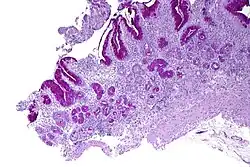

| Micrograph showing nodular enterochromaffin-like cell hyperplasia, as demonstrated with chromogranin A immunostaining, in the body of the stomach. Parietal cells are not readily apparent. These changes are in keeping with autoimmune metaplastic atrophic gastritis, a histologic correlate of vitamin B12 deficiency anemia. | |